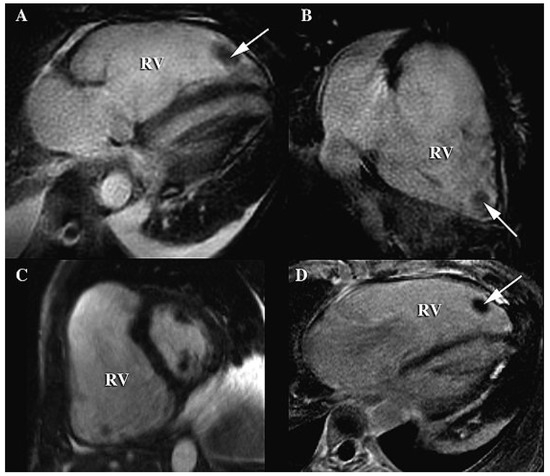

Just Pulmonary Embolism?

by Amir-Ali Fassa, Dominique Didier and Haran Burri

A 47-year-old female presented sudden loss of consciousness. On the arrival of the medical team the initial cardiac rhythm was ventricular fibrillation, which was successfully treated with cardiopulmonary resuscitation (CPR) and electric defibrillation […] Full article

Figure 1